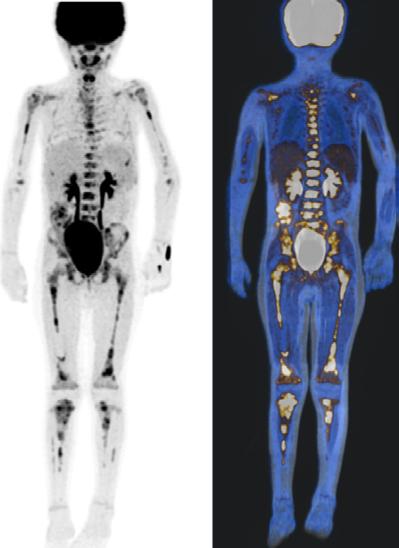

Figura 1A) Estudio PET con 6-[18F]FDOPA positivo para actividad tumoral del primario conocido en abdomen y retroperitoneo, con metástasis difusas en la médula ósea del esqueleto axial y apendicular.

Figura 1B) Estudio PET con [18F]OCTREOTIDE con sobreexpresión anormal de los receptores de somatostatina en retroperitoneo y esqueleto axial y apendicular.

Al correlacionar con 6-[18F]DOPA (Figura 1A) se observa que las lesiones tienen mayor sobreexpresión de los receptores de somatostatina.

El objetivo de este caso es mostrar la precisión diagnóstica que ofrecen los diversos radiofármacos, al realizar una correcta elección de acuerdo a la naturaleza biológica del neuroblastoma y a su expresión molecular.

Femenino de 7 años con diagnóstico de Neuroblastoma, se realiza PET/RM con [18F]F-DOPA para estadiaje, con evidencia de lesión primaria a nivel de retroperitoneo y conglomerados locoregionales así como infiltración a médula ósea del esqueleto axial y apendicular (Figura 1A), posteriormente la paciente fue tratada quirúrgicamente con resección de la lesión primaria así como tratamiento con inmunoterapia y transplante autólogo de médula ósea además de radioterapia. Al presentar refractariedad al tratamiento comentado, se plantea la posibilidad de administrar Lutecio (177Lu) oxodotreotide, por lo que se sugiere realizar PET/RM con [18F]Octreotide para valorar expresión de receptores de somatostatina y considerar la terapia con radionúclidos para receptores de péptidos (PRRT), el estudio muestra evidencia de sobreexpresión anormal de dichos receptores en retroperitoneo, espacio subpleural izquierdo además de esqueleto axial y apendicular (Figura 1B).